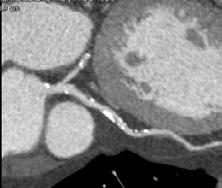

Figura 1. Pacient de 57ani cu simptomatologie acută sugestivă pentru AVC ischemic acut: CT -ul nativ nu a decelat elemente de semiologie sugestive pentru AVC ischemic acut (A), însă secvențele IRM au evidențiat o arie în hipersemnal FLAIR (B) și cu restricție de difuzie (C) localizată occipital paramedian dreapta, sugestivă pentru AVC ischemic acut (Spitalul Clinic de Urgență „Prof. N. Oblu“, Iași)

În contrast, imagistica prin rezonanță magnetică, în special secvențele de difuzie, oferă o sensibilitate superioară pentru detectarea precoce a infarctului ischemic,

fiind capabilă să identifice modificări la nivel celular la doar câteva minute după debutul simptomelor (Figura 1) (Mouridsen et al., 2020), (Nukovic et al., 2023). De asemenea, IRM este capabilă să ofere o evaluare superioară a integrității parenchimului cerebral, a viabilității țesutului și a extinderii leziunii ischemice, facilitând o caracterizare mai detaliată a AVC-ului ischemic (Cortés-Albornoz et al., 2025).